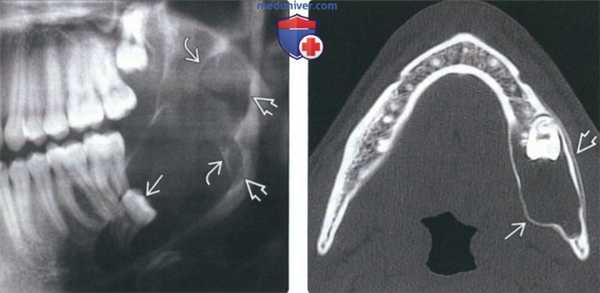

(Слева) При аксиальной КТ с контрастным усилением в задних отделах тела и ветви нижней челюсти визуализируется экспансивное объемное образование с диффузно низкой плотностью (кератокистозная одонтогенная опухоль). Образование не накапливает контраст. Целостность наружного кортикального слоя нарушена, в то же время опухоль остается отграниченной и не прорастает в жевательную мышцу. Отчетливо определяется асимметрия контуров щеки.

(Справа) При корональной КТ без КУ определяется легкое расширение нижней челюсти в области угла, обусловленное кератокистозной одонтогенной опухолью, и более выраженное расширение, а также истончение кортикального слоя выше (в области дуги). (Слева) При МРТ Т1ВИ в аксиальной проекции в нижней челюсти визуализируется неоднородное объемное образование, нарушающее целостность кортикального слоя и распространяющееся в жевательные мышцы. Участки с гиперинтенсивным сигналом в образовании, наличие которых является типичным признаком кератокистозной одонтогенной опухоли, обусловлены кератиновым дебрисом.

(Справа) При МРТ Т2ВИ в корональной проекции визуализируется объемное образование (кератокистозная одонтогенная опухоль) с гиперинтенсивным сигналом, характерным для жидкости. Также отмечается отсутствие инфильтрации прилежащих к опухоли тканей, несмотря на то, что она распространяется в жевательное пространство кнутри, а также кнаружи. (Слева) При аксиальной КТ в костном окне в задних отделах тела нижней челюсти справа визуализируется однокамерное кистозное образование, приводящее к легкому вздутию кости и бугристости кортикального слоя, но не к нарушению его целостности. Визуализируется интактный третий моляр с противоположной стороны (слева).

(Справа) При аксиальной КТ в костном окне на более каудальном уровне у этого же пациента визуализируется непрорезавшийся третий моляр справа, связанный с кистозным образованием. Такие изменения чаще всего обусловлены зубосодержащей киаой; тем не менее, при патоморфологическом исследовании подтвердилась кератокистозная одонтогенная опухоль.